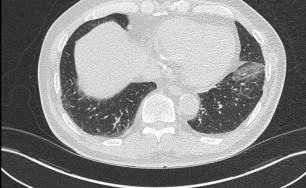

기관지확장증의 CT 사진

비결핵항산균에 감염된 폐사진